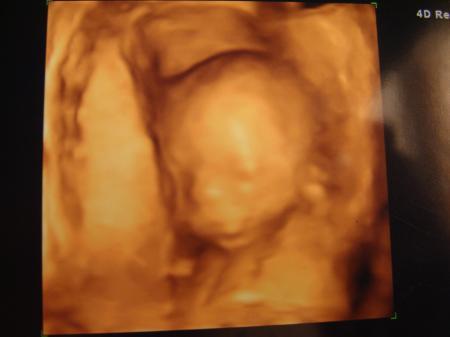

Hallo Mädels! Also es bleibt dabei....es wird ein Bub! Beweisfoto im Anhang! Das muss man einfach erkennen. Er ist zeitgemäß entwickelt und seine Organe ohne Auffälligkeiten. Gewicht und Größe konnte er mir nicht sagen. Nur das er bei 21/22 mm liegt. Hab mich schon total in ihn verliebt. Ein hübscher Junge. Nur mein Gebärmutter Puls (glaube so hieß es) wäre nicht so toll (irgendwas ist ja immer) Muss jetzt Blutverdünner nehmen, weil der Mutterkuchen jetzt dabei wäre sich richtig aufzubauen und da braucht es wohl die Unterstützung dazu. Sein Herz konnte er auch nicht richtig sehen, da er mit dem Rücken zu uns lag. In 4 Wochen darf ich nochmal kommen und dann schaut er sich nochmal das Herz und den Puls an. Dann waren wir endlich Heim und er hat mich dann getreten, damit ich mich endlich mal hinlege.... ...aber Auto fahren fand er toll, nur anhalten war im zu langweilig

Bild zu Heute FD Termin - Forum für August - Mamis